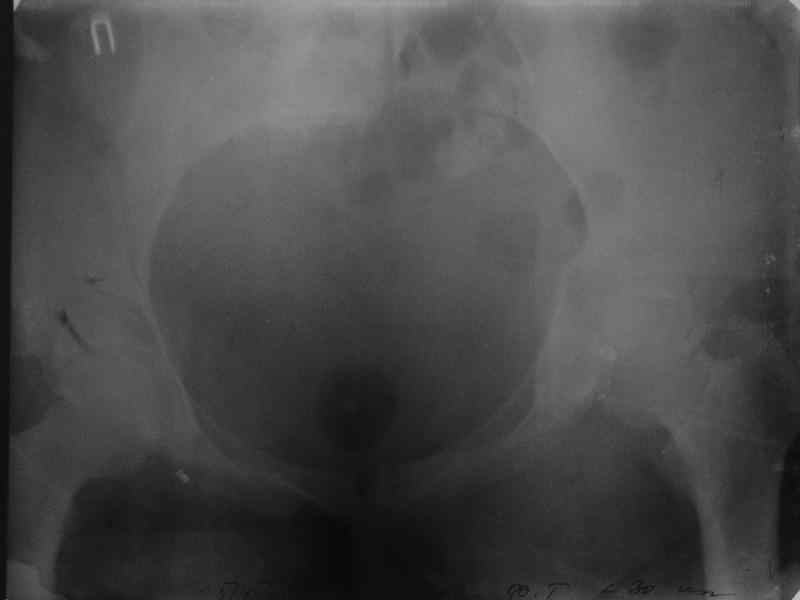

Здравствуйте, коллеги. Какие будут мнения по поводу лечения представляемой больной?

Молодая девушка 19 лет, травма 1 год назад, тогда же прооперирована.

В настоящее время имеются ноющие боли в области крестца слева, нарушение походки, ощущение неуверенности, слабости в левой нижней конечности, неврологически -непостоянные парестезии в левой нижней конечности. Ходит с дополнительной опорой, страдает от ожирения.

Какова по вашему будет оптимальная тактика в отношении несращения крестца? Замена винтов на более длинные с коррекцией их положения+ туннелизация зоны нестращения, открытое вмешательство с костной аутопластикой или еще какие варианты?

В приложении снимки при поступлении и послеоперационные год назад.